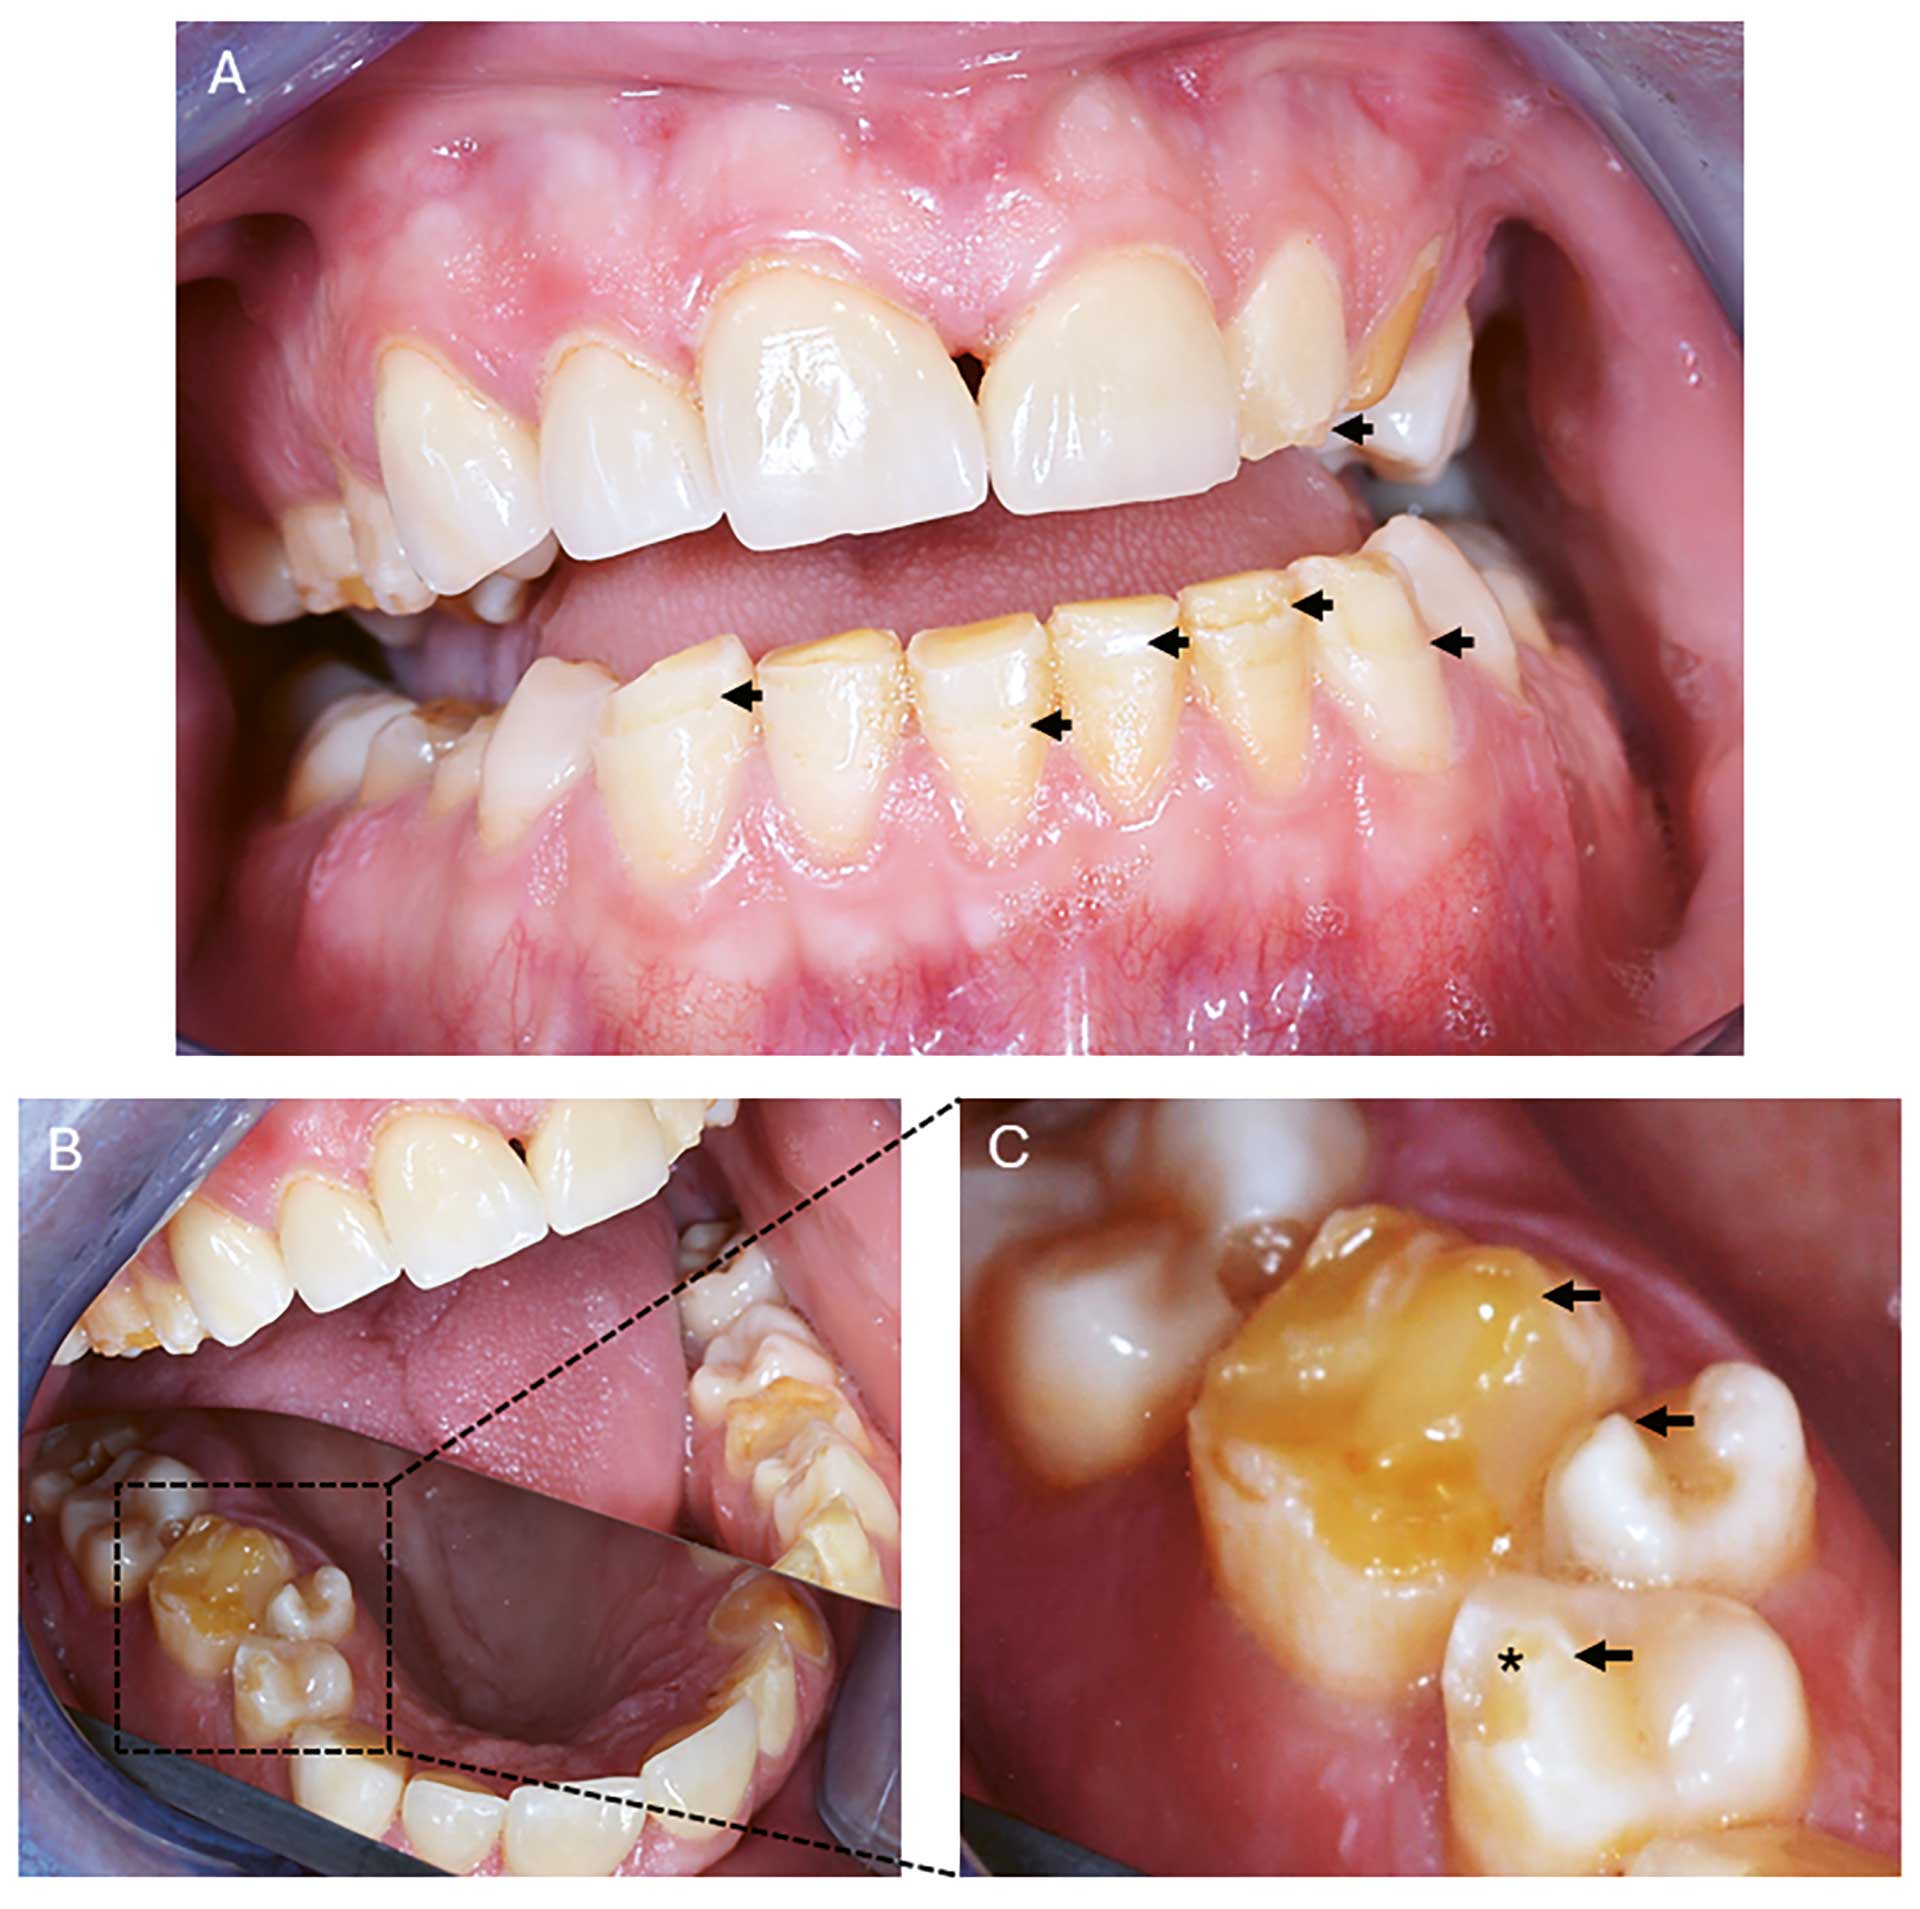

Figur 2

Figur 2. Klinisk foto av orale manifestasjoner hos pasient 1. (A) Emaljehypoplasi kan sees på 22, 31, 32, 33, 41 og 43 (svarte piler) (B) Oversiktsbilde av 1. kvadrant ved hjelp av speil (stiplet område). (C) Større forstørrelse av tann 16, 15 og 14 i B med emaljehypoplasi (svarte piler) og 14 med fraktur av emalje på kuspetopp (stjerne).

Intraoral undersøkelse: Normale slimhinner uten tegn til candidainfeksjon. Flere tenner hadde komposittrestaureringer. Det var også tydelig tannslitasje i form av erosjon og abrasjon på flere tenner. Hypoplastiske emaljedefekter kunne sees på flere tenner i alle kvadranter. Tann 23 har slitasje til dentin. Det registreres hypoplasi, men for noen av disse defektene kan posteruptive brekkasjer ikke utelukkes. Hypoplasi ble registrert bukkalt/okklusalt på tann 14, 16, 22, 24, 25, 26, 33, 32, 31, 41, 42, 43 (figur 2). Hypoplasi lingualt i form av furer ble observert på tann 33 og 43. Multiple kariesangrep ble også diagnostisert, men kun symptomer fra tann 16 med behov for endodontisk behandling.